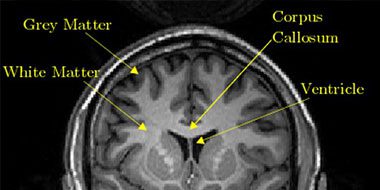

Grey is the new White? Not in the brain!

This Science Facts blog explains the difference between white and grey matter in the brain. Helping you untangle complex concepts and language in research studies!

Grey Matter Brain Damage

This blog explains the difference between white and grey matter injuries and their effects on the brain.